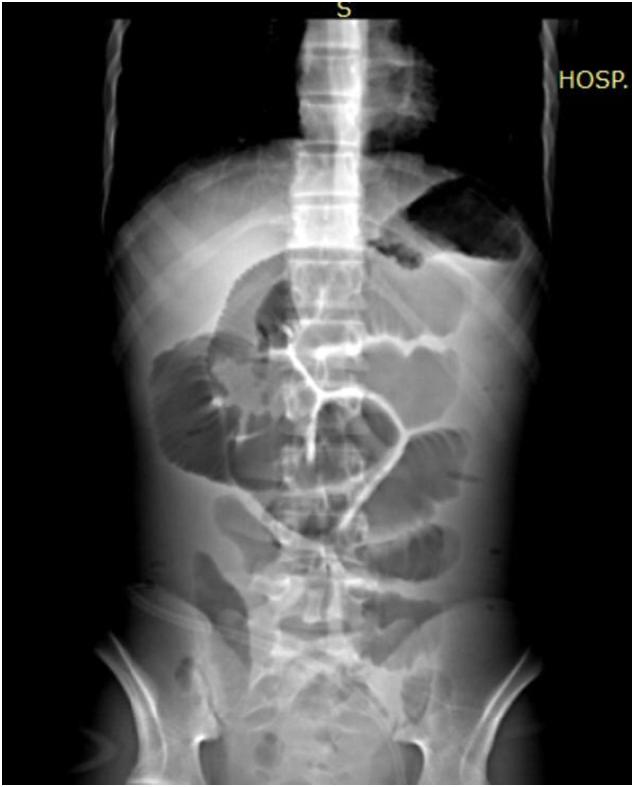

Herein, we report the case of a 14-year-old boy with familial adenomatous polyposis who underwent total proctocolectomy, ileal pouch-anal anastomosis, and diverting ileostomy. The patient developed early postoperative complications; on postoperative day 1, he developed bleeding from the pouch staple line, which was managed endoscopically. On postoperative day 15, he developed intestinal obstruction due to adhesions. One year after proctocolectomy, ileostomy closure was performed uneventfully. From postoperative day 3, the patient presented with obstructive signs such as abdominal distention, bloating, abdominal pain, and fever. Computed tomography identified diffuse intense intestinal distension with pouch dilatation. Digital rectal examination identified the pouch filled with liquid stool and no signs of anal canal anastomosis stenosis. The patient was considered to have pouch outlet obstruction and was successfully managed using bedside evacuation anoscopy. After 3 days, oral nutrition was re-established, and appropriate stool evacuation and fecal continence were achieved.

We presented an unusual case of acute intestinal obstruction due to pouch outlet obstruction that was managed nonoperatively with bedside pouch evacuation.